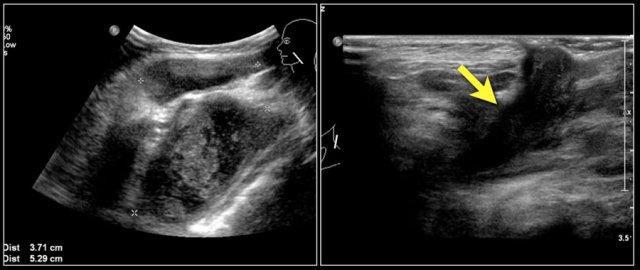

Đây là hình ảnh siêu âm của một bé gái sáu tuổi với tình trạng sưng đột ngột ở cổ bên trái.

Có nhiều nang nhỏ không có âm vang và một nang lớn chứa các âm vang bên trong, có thể là kết quả của xuất huyết trong một u bạch huyết mạch có sẵn từ trước.

Một bé trai 3 tuổi đột ngột xuất hiện khối u vùng trên xương đòn.

Ultrasound showed a lesion with echogenic debris.

A hemorrhage in a preexisting lymphangioma was suspected.